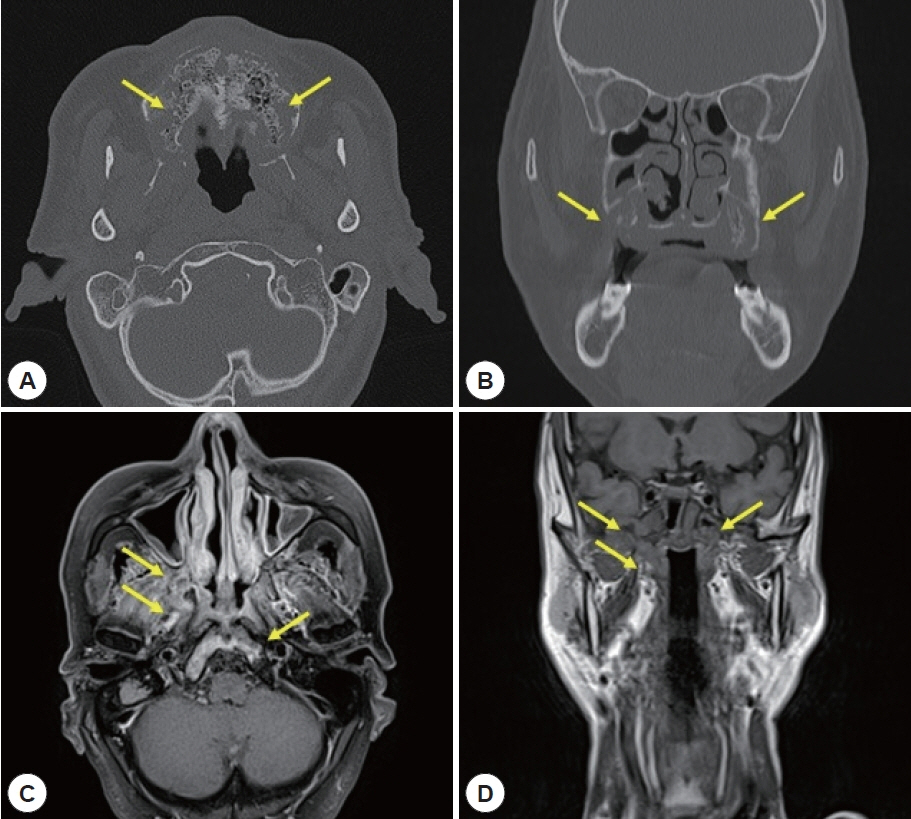

- Central skull base osteomyelitis (CSBO) is a rare, fatal condition seen mostly in elderly diabetic or immunocompromised patients; it mainly involves the sphenoid or occipital bones and diagnosis is often delayed. A 72-year-old male with diabetes was referred to our department with severe pain in the maxillary gingiva. Endoscopic biopsy of the pterygoid bone confirmed the presence of mucormycosis combined with Klebsiella pneumoniae infection. Sinus surgery was performed with bilateral alveolar bone sequestrectomy. Long-term intravenous broad-spectrum antibiotic therapy using meropenem and ampicillin/sulbactam and antifungal therapy using amphotericin B (100 mg/day) was administered; an oral antifungal agent, posaconazole (800 mg/day), was also prescribed for 11 weeks. At the 6-month follow-up visit, there were no complications and no progression of the CSBO lesion was observed. Timely diagnosis and multidisciplinary treatment including endoscopic surgery, alveolar bone sequestrectomy, and combined antifungal and antibiotic therapy can reduce mortality and minimize complications associated with CSBO.

Figure